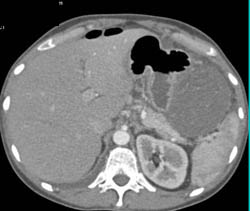

Antral Carcinoma